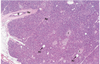

Endocrine Pancreas

D interlobular duct Ac adipocyte I islet of Langerhans Sp septum